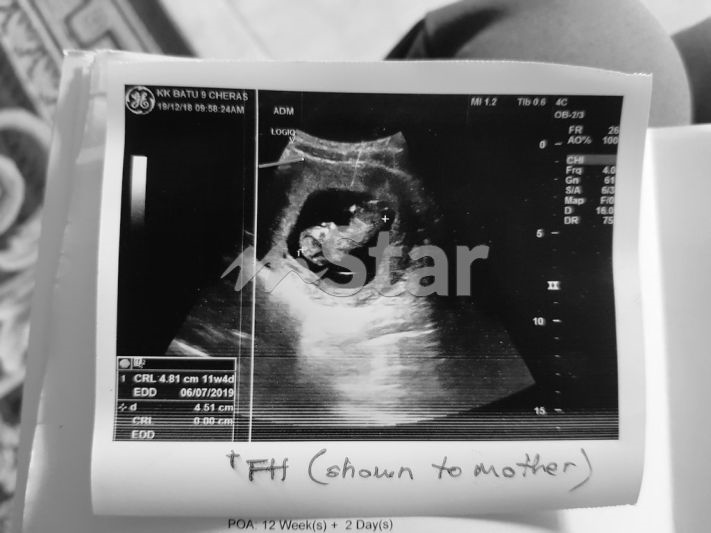

Bukan sahaja kehilangan ibu, wanita ini turut kehilangan bayi dalam kandungannya yang ketika itu berusia hampir empat bulan.

Bayi yang berusia hampir empat bulan dalam kandungan gugur gara-gara kemalangan yang menimpa Nadia pada tahun lalu.

“Buah pinggang luka, paru-paru terpaksa ditebuk, tulang pinggul dan tulang rusuk retak dan kepala mengalami gegaran. Bayi dalam kandungan gugur selepas itu kerana saya perlu di x-ray dan dimasukkan morfin. Doktor terpaksa selamatkan ibu dahulu,” ceritanya.